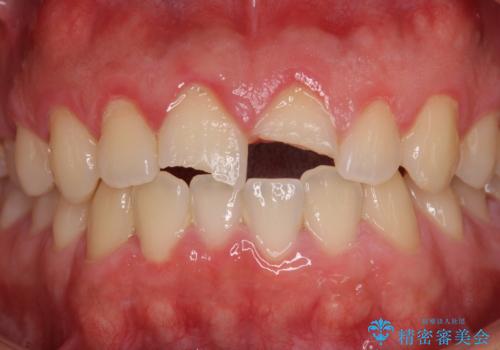

- 酔っ払って転んだらしく、目が覚めたら病室で歯が欠けていたとのことで来院された患者様です。

痛みを感じており、歯の欠けている状況から、神経組織のダメージも想定されました。

無菌的環境下にて歯の状態を調べ、最終的にオールセラミッククラウンにて補綴治療を行うこととしました。